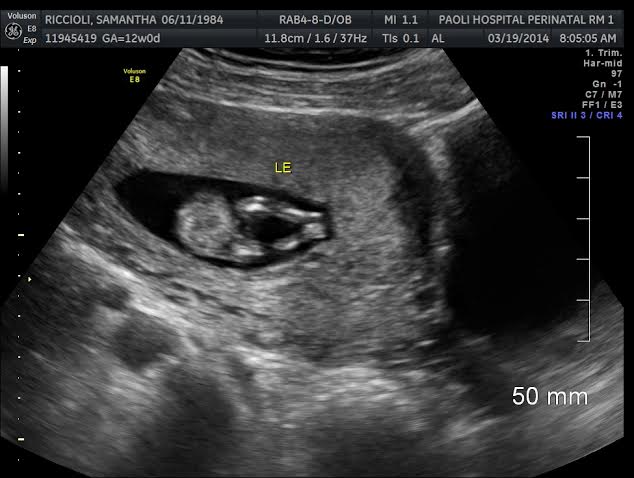

Anyone know about 3 dot theory? I know girls and boys have swollen similar parts at this stage but what do you think? Attachment 17914Attachment 17915

It looks like a boy but at this gestation, I would prefer to see the side nub view. It could go either way.

At 12 weeks on the dot I wouldn't even pay attention to a potty shot. You are seeing the nub from underneath. That nub could be sticking straight out and be girly. It could also be headed upward and be boyish. I would say it's 50-50. I wouldn't put stock into it.

Swollen girly bits to me xx